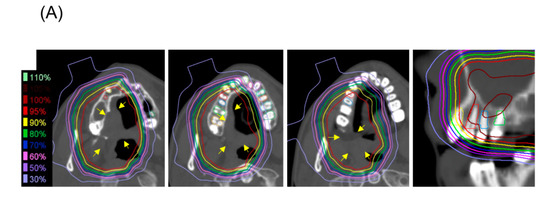

Figure 1.

A representative patient with mucoepimoid carcinoma (yellow arrow) of the hard palate who experienced tooth loss after carbon ion radiotherapy (CIRT) with 64 Gy (relative biological effectiveness) delivered in 16 fractions. (A) Treatment planning computed tomography (CT) images showing isodose lines and the contours of the teeth (the three left-most images are axial sections and the right-most image is a coronal secton). (B) CT images taken 5 years post-CIRT.

The present study enrolled 14 patients (Table 1) and 171 teeth identified on pre-CIRT examination were analyzed. Primary tumor sites were located mainly in the nasal cavity and maxillary sinus, which are adjacent to the maxillary teeth. Adenoid cystic carcinoma was the most common histological type. Most patients received a dose of 64.0 Gy (RBE), delivered in 16 fractions. The median follow-up period was 69.1 months (range, 38.6–96.5 months). During follow-up, loss of 25 teeth was observed. One of the 25 lost teeth was excluded for the analysis because the p-value assessed by the Smirnov–Grubbs’ test was below <0.05 for V10, V20, V30, V40, V50, and V60, suggesting that the loss of this tooth was unrelated to CIRT (Supplementary Figure S1). Figure 1 shows a representative case of tooth loss; at 5 years post-CIRT, a part of the alveolar bone of the maxilla, which received high-dose carbon ions, disappeared and resulted in the loss of four teeth.

In addition to radiation, causes of tooth loss include caries and periodontal disease [30,31,32]. Furthermore, tumor invasion into the maxilla may be a factor that affects tooth loss after treatment. This study did not examine these factors. However, none of the patients lost teeth due to extractions caused by tooth decay in this study. In order to clarify the relationship between the irradiated dose and tooth loss, we excluded patients who did not have irradiated teeth. Of the 25 teeth lost, one was excluded from the analysis because it was clearly an outlier in terms of the irradiated dose; therefore, we assumed that loss of this tooth was caused by factors other than radiation. Regarding loss of the other 24 teeth, we noted that the maxillary bone that supported these teeth disappeared. These changes occurred in line with the distribution of high-dose irradiation in CIRT (Figure 1B) and were uncommon with photon radiotherapy. Clinically, we believe that tooth loss is related to the loss of maxillary bone and evaluated the dose of only the root part and not the crown part in this study. The dosimetric parameters for the root part predicted tooth loss with high accuracy. If factors other than irradiation, such as caries and periodontal disease, had a greater influence, the relationship between dosimetric parameters and tooth loss would not be so clear. Taken together, we consider that factors other than irradiation had a small effect on the loss of the teeth analyzed herein. If these cutoffs can be adhered to, then tooth loss can be prevented in most cases.